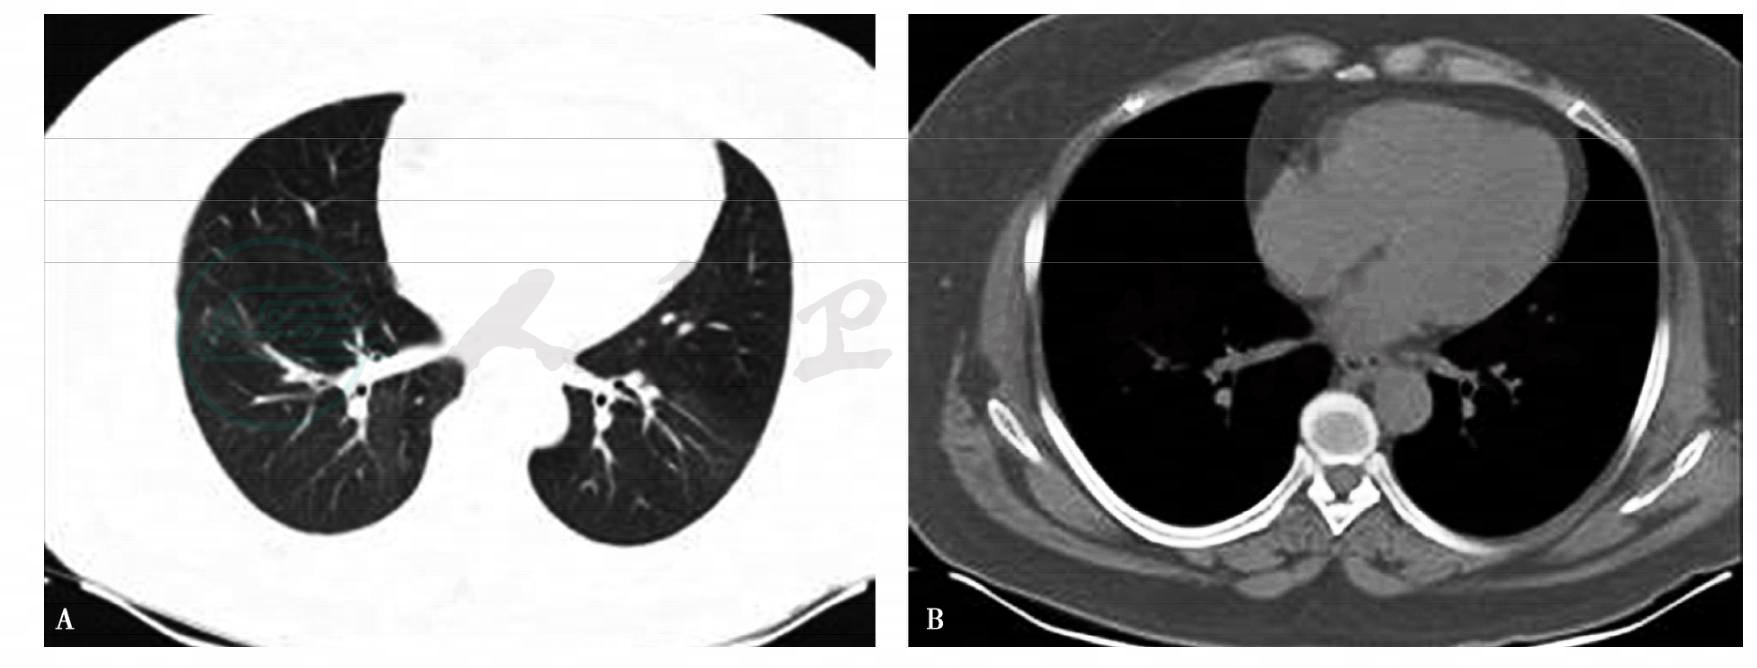

7.胸部CT(2011年6月1日):双肺多发斑片状密度增高影,以下肺、周围为主,内有支气管充气征(图1A肺窗、B纵隔窗)。

图1 胸部CT(2011年6月1日)